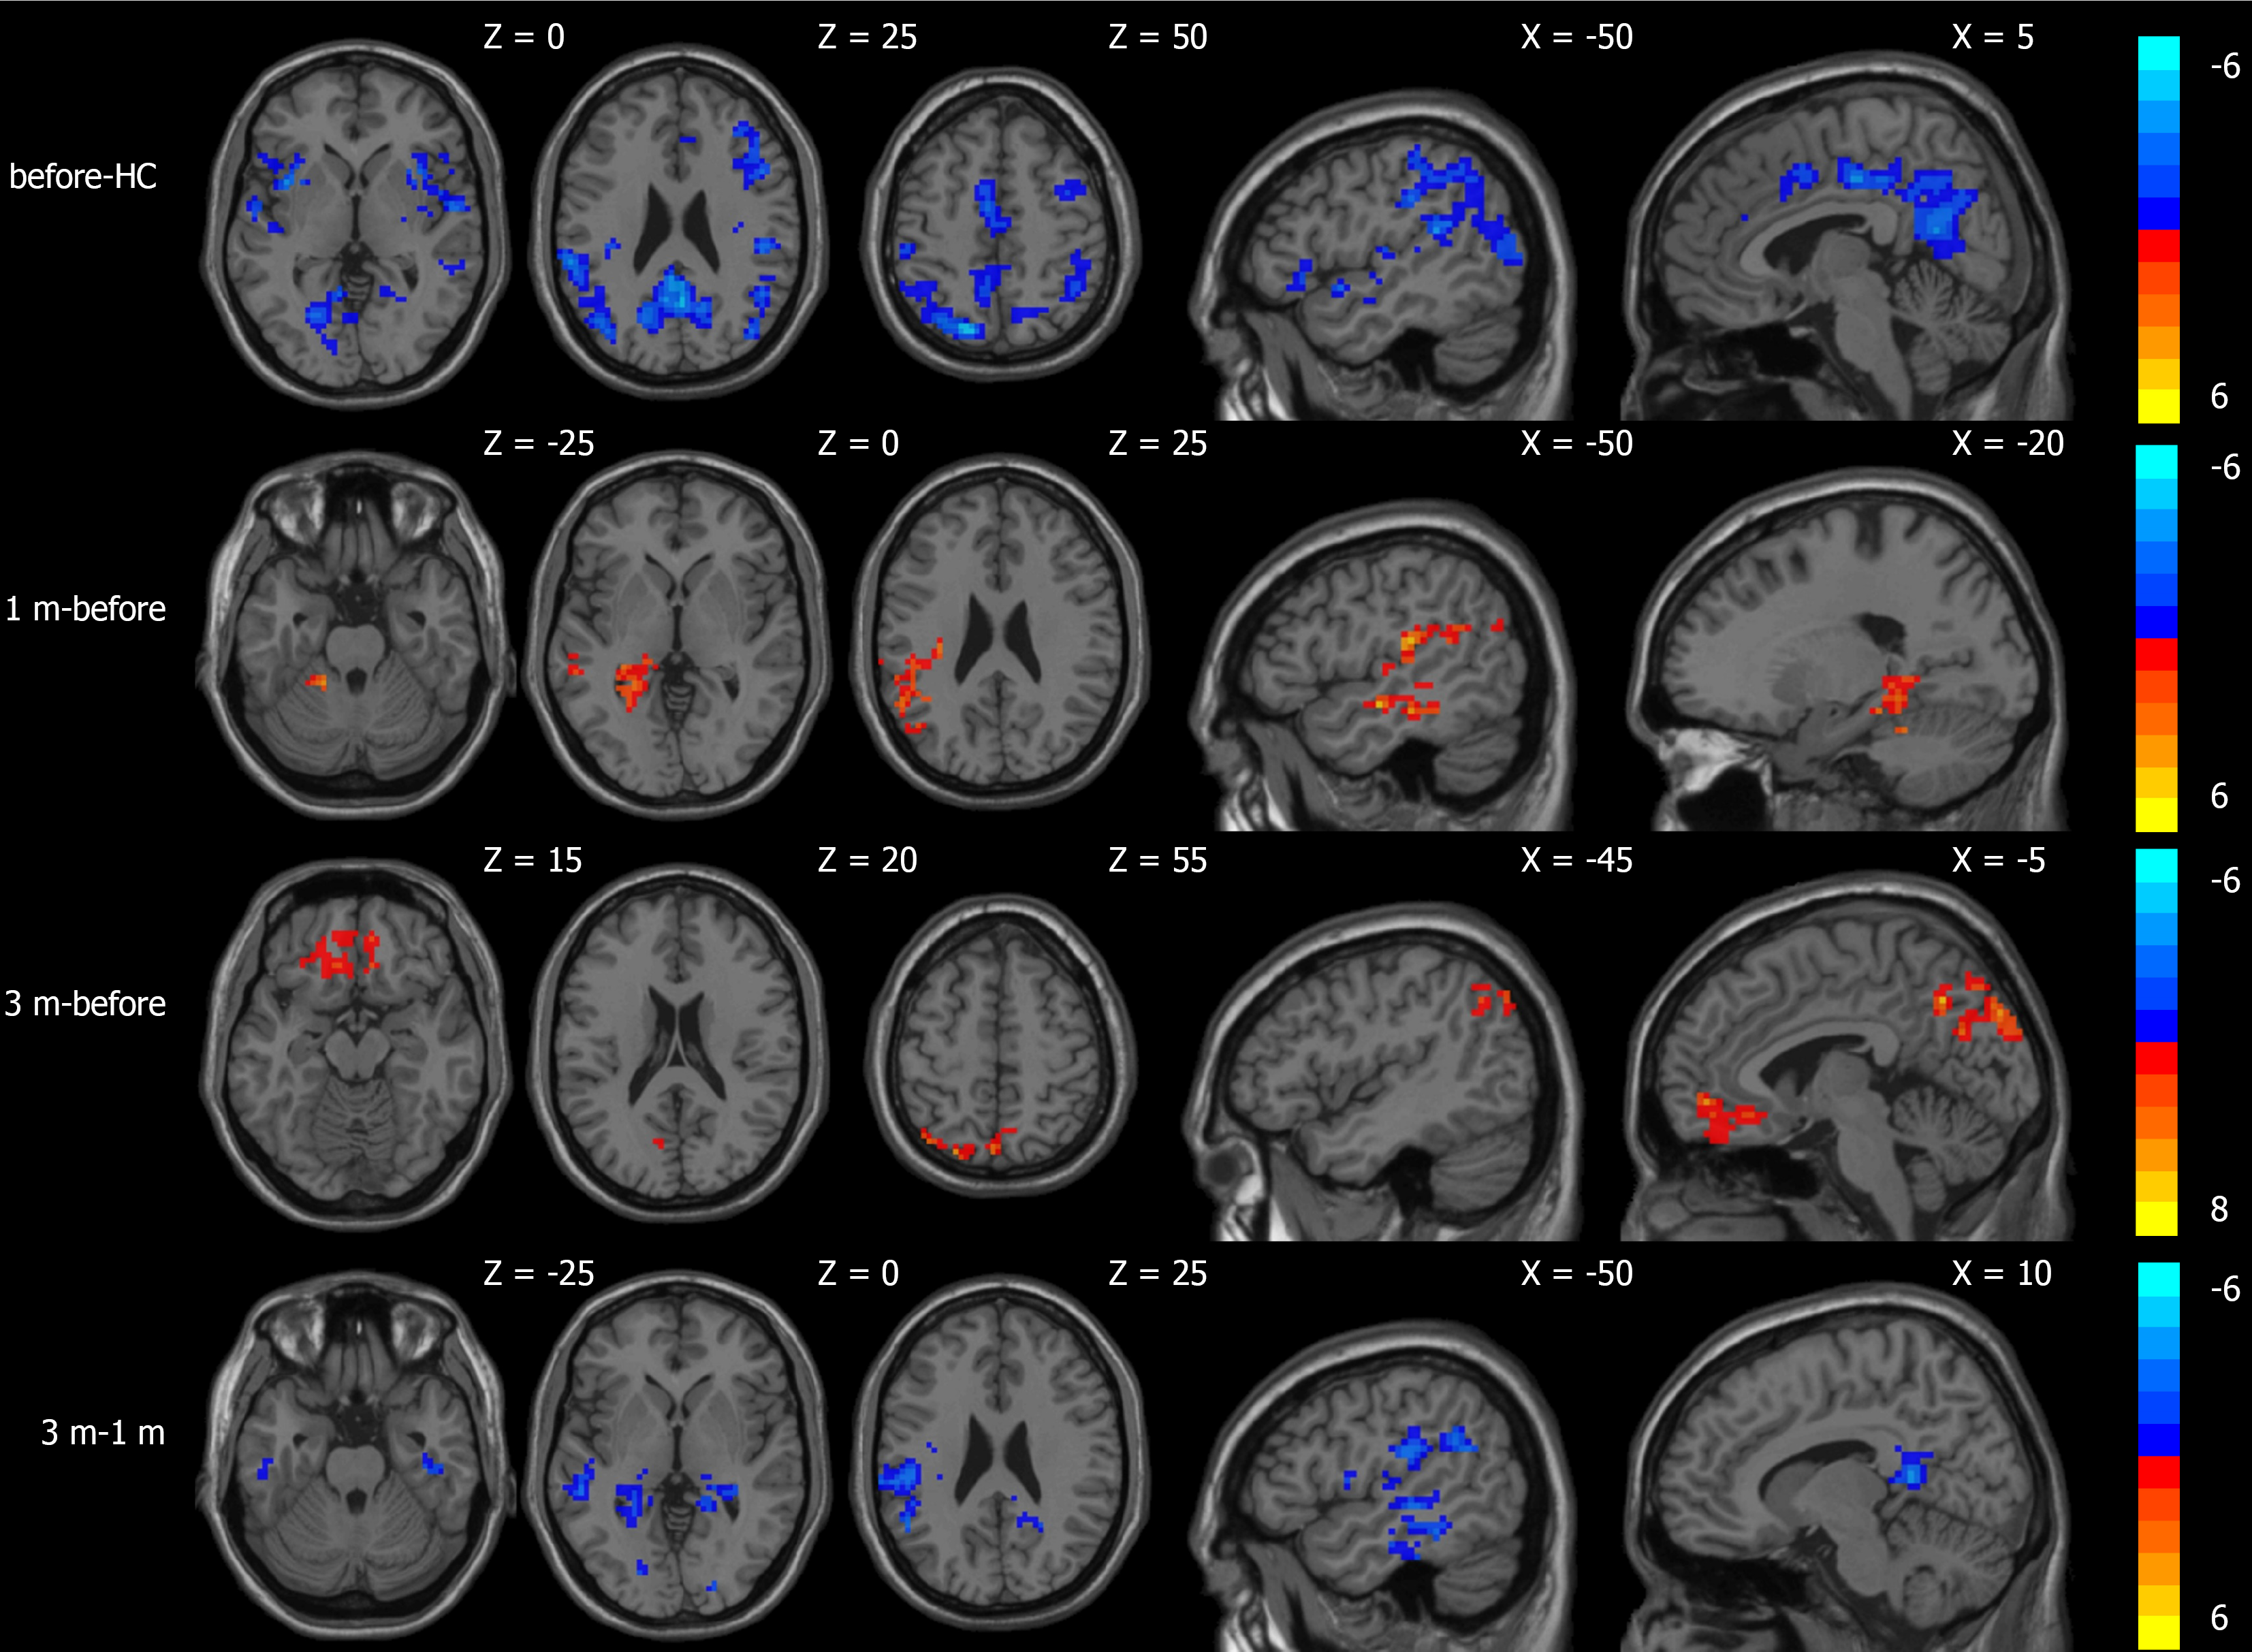

Compared to the normal control group, the CBF values of patients with portal hypertension and cirrhosis decreased in the area centered on the right orbitofrontal gyrus and the left superior temporal gyrus. The ALFF values decreased in the area centered on the left superior temporal gyrus, the left inferior frontal gyrus of the operculum, and the right precuneus. Compared to before TIPS, the CBF values increased in the area centered on the left fusiform gyrus 1 month after TIPS. The ALFF values increased in the area centered on the left superior temporal gyrus; there were no areas with significant CBF differences 3 months after TIPS. The ALFF values increased in the area centered on the left orbitofrontal gyrus and the left precuneus 3 months after TIPS. In comparison to 1 month after TIPS, CBF values decreased in the area centered on the right fusiform gyrus and increased in the area centered on the left angular gyrus 3 months after TIPS. ALFF values decreased in the area centered on the right insula and the cerebellum (Table 2; Figures 2 and 3).

| Group | Brain regions | MNI coordinates (mm) | Volume (mm3) | Peak (t-value) | ||

| X | Y | Z | ||||

| Comparison results of ALFF differences | ||||||

| Before-HC | L. superior temporal gyrus | -39 | -33 | 12 | 1502 | -6.68 |

| L. opercular part of inferior frontal gyrus | -48 | 9 | 21 | 213 | -6.36 | |

| R. precuneus | 15 | -60 | 21 | 3765 | -6.04 | |

| 1 m-before | L. superior temporal gyrus | -48 | -30 | 21 | 687 | +4.68 |

| 3 m-before | L. orbitofrontal superior gyrus | -6 | 51 | -6 | 298 | +5.95 |

| L. precuneus | -3 | -75 | 51 | 458 | +7.69 | |

| 3 m-1 m | R. insula | 36 | -27 | 18 | 513 | -6.43 |

| Cerebelum_Crus1_L | -24 | -72 | -33 | 851 | -6.64 | |